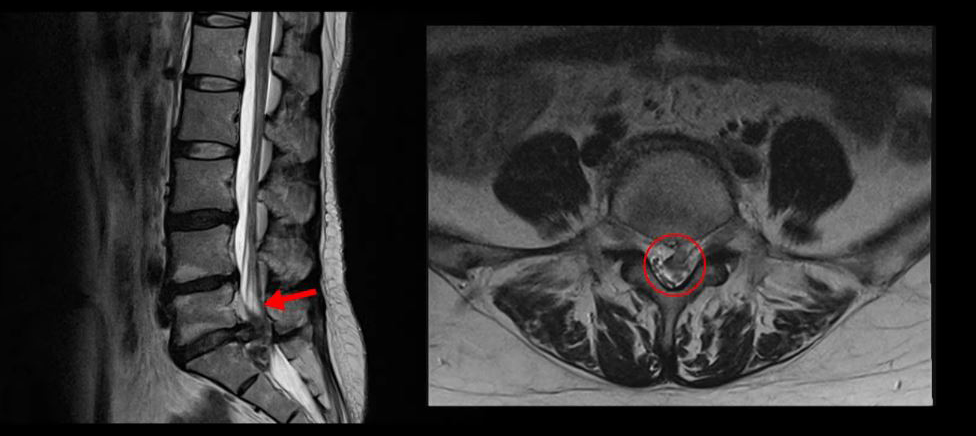

<5-1번 디스크 파열>

이 환자분의 허리 MRI를 보면 5번, 1번 디스크가 매우 심하게 터져 있는 것이 보입니다. 굉장히 심한 허리디스크터짐으로 인해 신경이 있어야 할 곳을 밀려나온 디스크 수핵이 거의 다 차지하고 있는 것을 볼 수 있습니다.

디스크가 심하게 터져서 수핵이 많이 밀려 나오니까 수핵이 위로도 밀려 올라가고 아래로도 흘러내려 있습니다.

축상면으로 보면 수핵이 위로도 밀려 올라가서 신경 공간을 까맣게 차지하고 있는 것이 보입니다.

아래로도 저 밑에까지 흘러내려가 신경 공간을 많이 차지하고 있어서 신경의 형태가 제대로 보이지가 않습니다.

MRI로 이 정도의 심한 파열이 보이면 다리에 마비나 대소변 장애까지도 있지 않을까 의심될 수 있는 상황인데요. 그래서 환자분이 MRI를 찍은 정형외과에서도 대소변 장애는 없는지 확인하였고, 파열이 심하니까 무조건 바로 수술을 해야 한다고 얘기했다고 합니다. 그런데 다행히도 이 환자분은 다리에 감각 마비와 보행 시 힘 빠짐 증상은 있으나, 대소변 장애는 없었습니다.